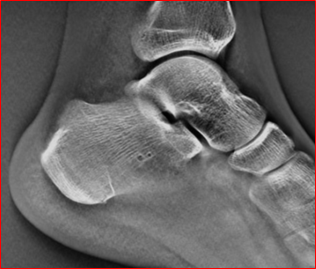

TOMOS 功能可以在一次扫描下,获得连续多层面的高清晰断层图像。 TOMOS 功能减少了因组织重叠造成的干扰,提高了病变检出的敏感性和特异性。即使是细微的骨折线,在它生成的清晰图像下,也能清晰呈现。

通过TOMOS,可见骨折线